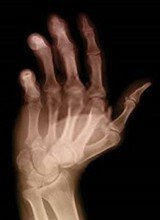

Artritis heilt mit

Borax  Gelenkschmerzen durch Artritis heilen mit

Borax  Knochenschwund (Osteoporose) heilt mit Borax  Karies

wird mit Borax vermindert

Artritis heilt mit Borax [3] - Gelenkschmerzen durch Artritis heilen mit Borax [4] - Knochenschwund (Osteoporose) heilt mit Borax [5] - Karies wird mit Borax vermindert [6] -

-- werden Arthritis, Artrose, Gelenkschmerzen und Osteoporosis (Knochenschwund, hohle Knochen) geheilt, auch Zähne werden stärker, und